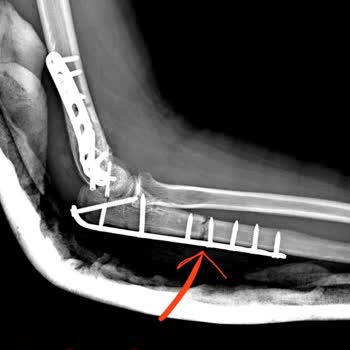

Fizik Tedavi Skandalı: Sağlam Dirsek Kemiği Kırıldı!

Ocak 2025 tarihinde fizik tedavi sırasında aşırı kuvvet uygulayarak sağlam dirsek kemiğimi kırdılar ve tekrar ameliyat olmak zorunda kaldım! Maddi ve manevi büyük zarar gördüm, ancak hatalarını kabul etmedikleri gibi muhatap bile olmadılar. Şikayetçiyim ve şu an davalık durumdayız. Önermiyorum. Zara...